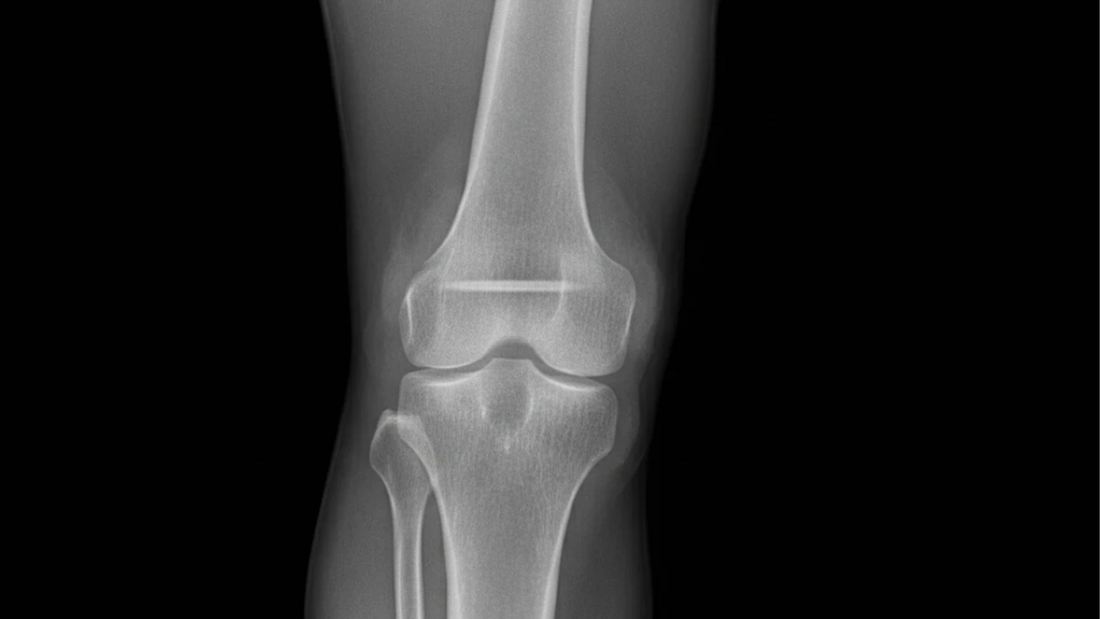

Joint effusion refers to the abnormal accumulation of fluid inside or around a joint (the joint’s intra‑articular space or associated bursae). The fluid may be synovial fluid (normally present in joints), blood (hemarthrosis), pus (in infection), or a mix depending on underlying cause. While many joints can be affected, it most often occurs in large weight‑bearing joints such as the knee, hip, or shoulder.

Diagnosis usually involves a physical exam, imaging (X-ray, ultrasound, MRI) and often synovial fluid analysis (arthrocentesis). Fluid analysis can reveal bacteria, crystals, or other markers to determine the cause (NCBI, 2024)